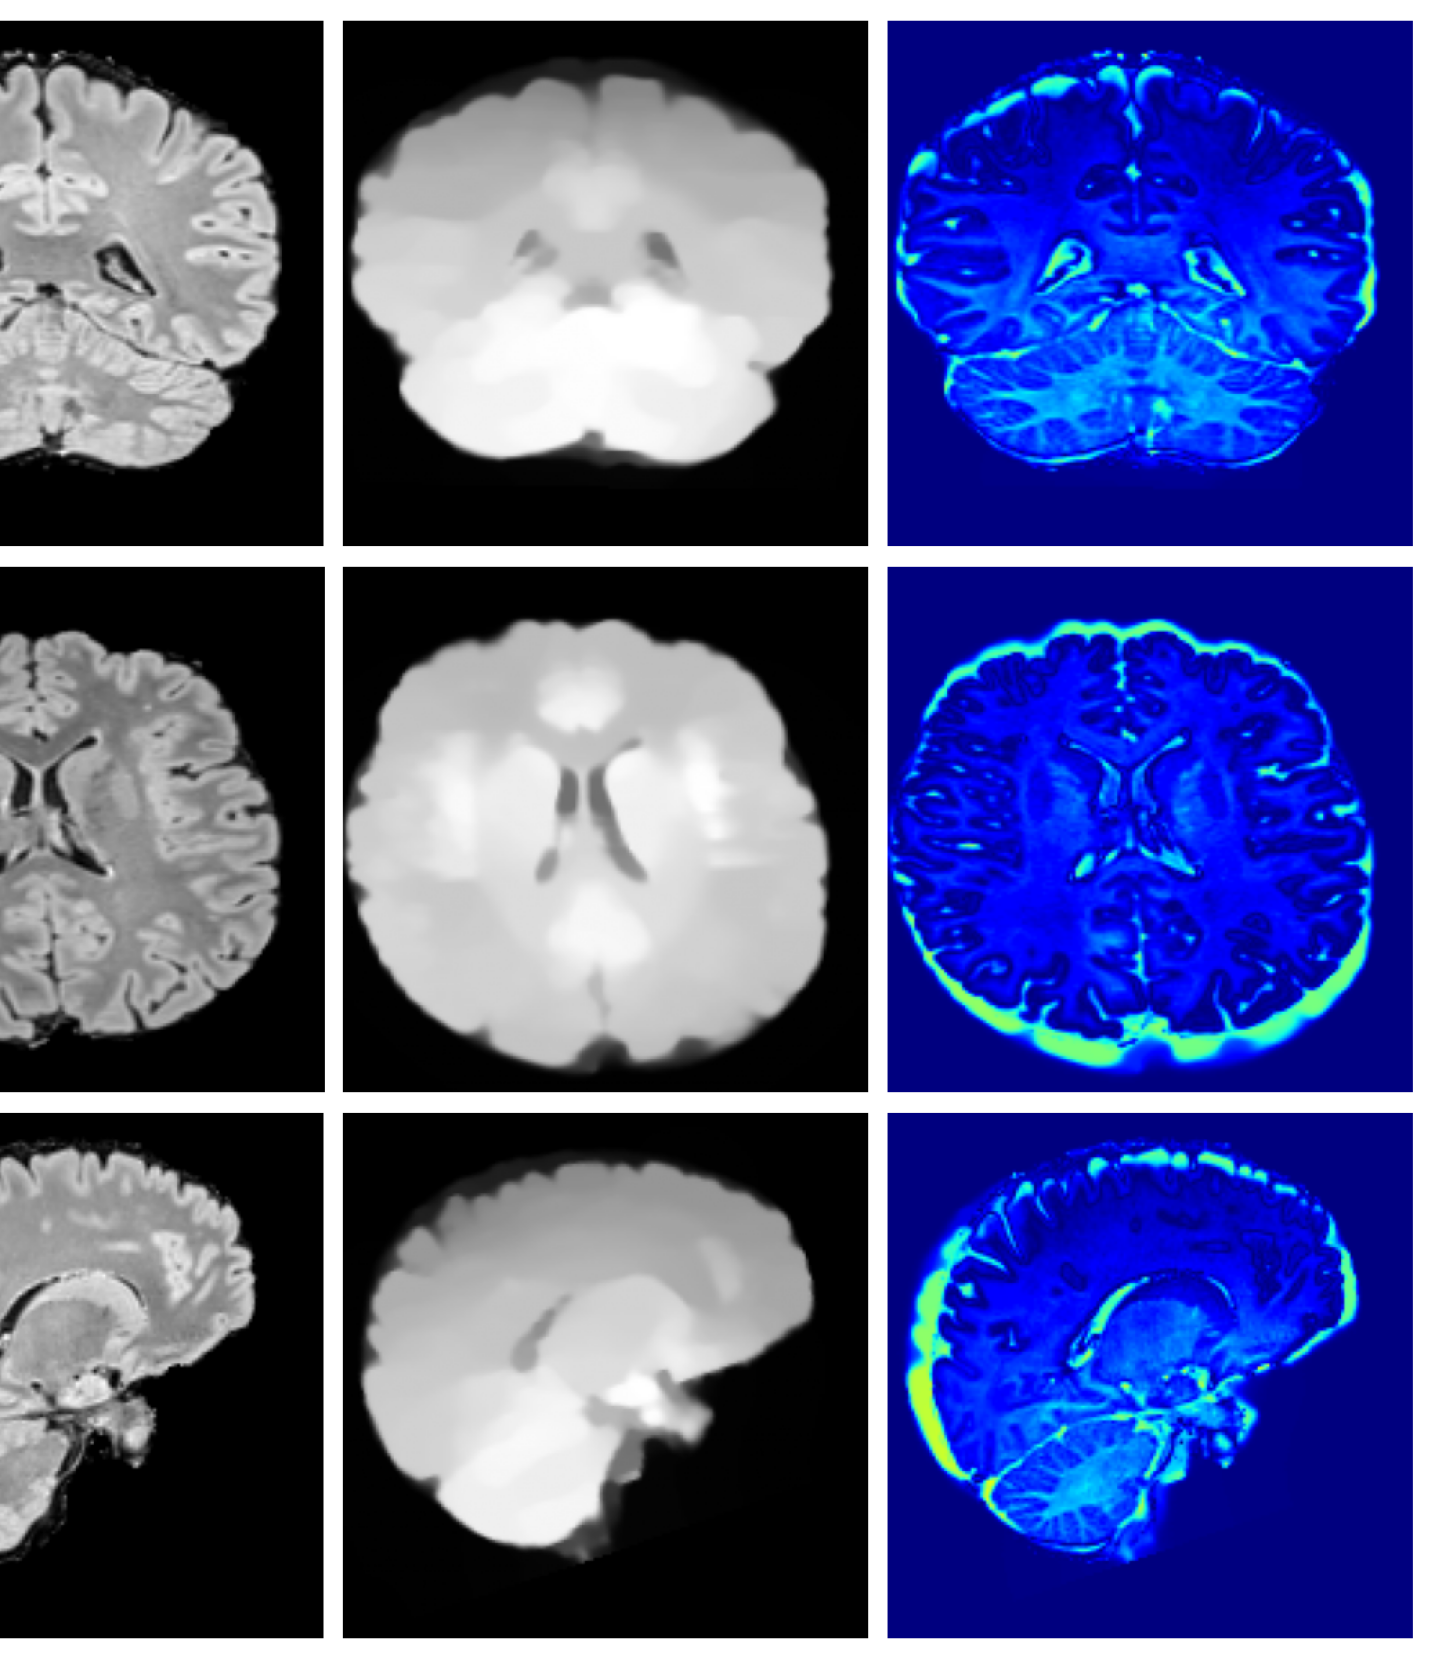

Qualitative T1w results are shown in Figure 2, with further examples for other modalities in Appendix A.8. LoHiResGAN and Res-SRDiff produce unrealistic images with severe artifacts, likely arising from bias fields, sharp intensity artifacts, and other noise not present during training. UniRes generates oversmoothed images, likely due to its TV prior and its reliance on information from multiple input modalities, whereas we apply it unimodally. Di-Fusion shows less pronounced but still notably blurry, voxelated reconstructions which lack the fine-grained details generate by our method. This is likely, in part, due to our use of synthetic rather than real noisy training data, which the method was designed for. As such data is scarce, and in our case unavailable, this requirement represents a significant limitation of Di-Fusion. SynthSR, whilst not as well as our method, does preserve key anatomical structures. However, our difference maps show reduced contrast, further supporting the strong quantitative results shown in Table 2.

A.8 Additional qualitative restoration results

Additional qualitative results for the Clinical dataset are given in Figures 7, 8 and 9, and for the Low-field dataset in Figures 10 and 11.